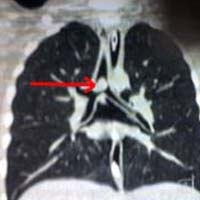

"Khi trên đường đến bệnh viện, anh ta hoàn toàn tỉnh táo mặc dù cây xiên cá đã đâm vào mắt trái anh ta, xuyên qua hộp sọ và chỉ cách động mạch chủ vài milimet. Anh ta thật sự là một người may mắn" - Một người bạn của nạn nhân cho biết.

Hiện bệnh nhân đang trải qua những ca phẫu thuật khẩn cấp trong tình trạng tổn thương nặng về hộp sọ, các bác sĩ cũng cho biết mắt trái của anh Coutinho sẽ rất khó phục hồi.